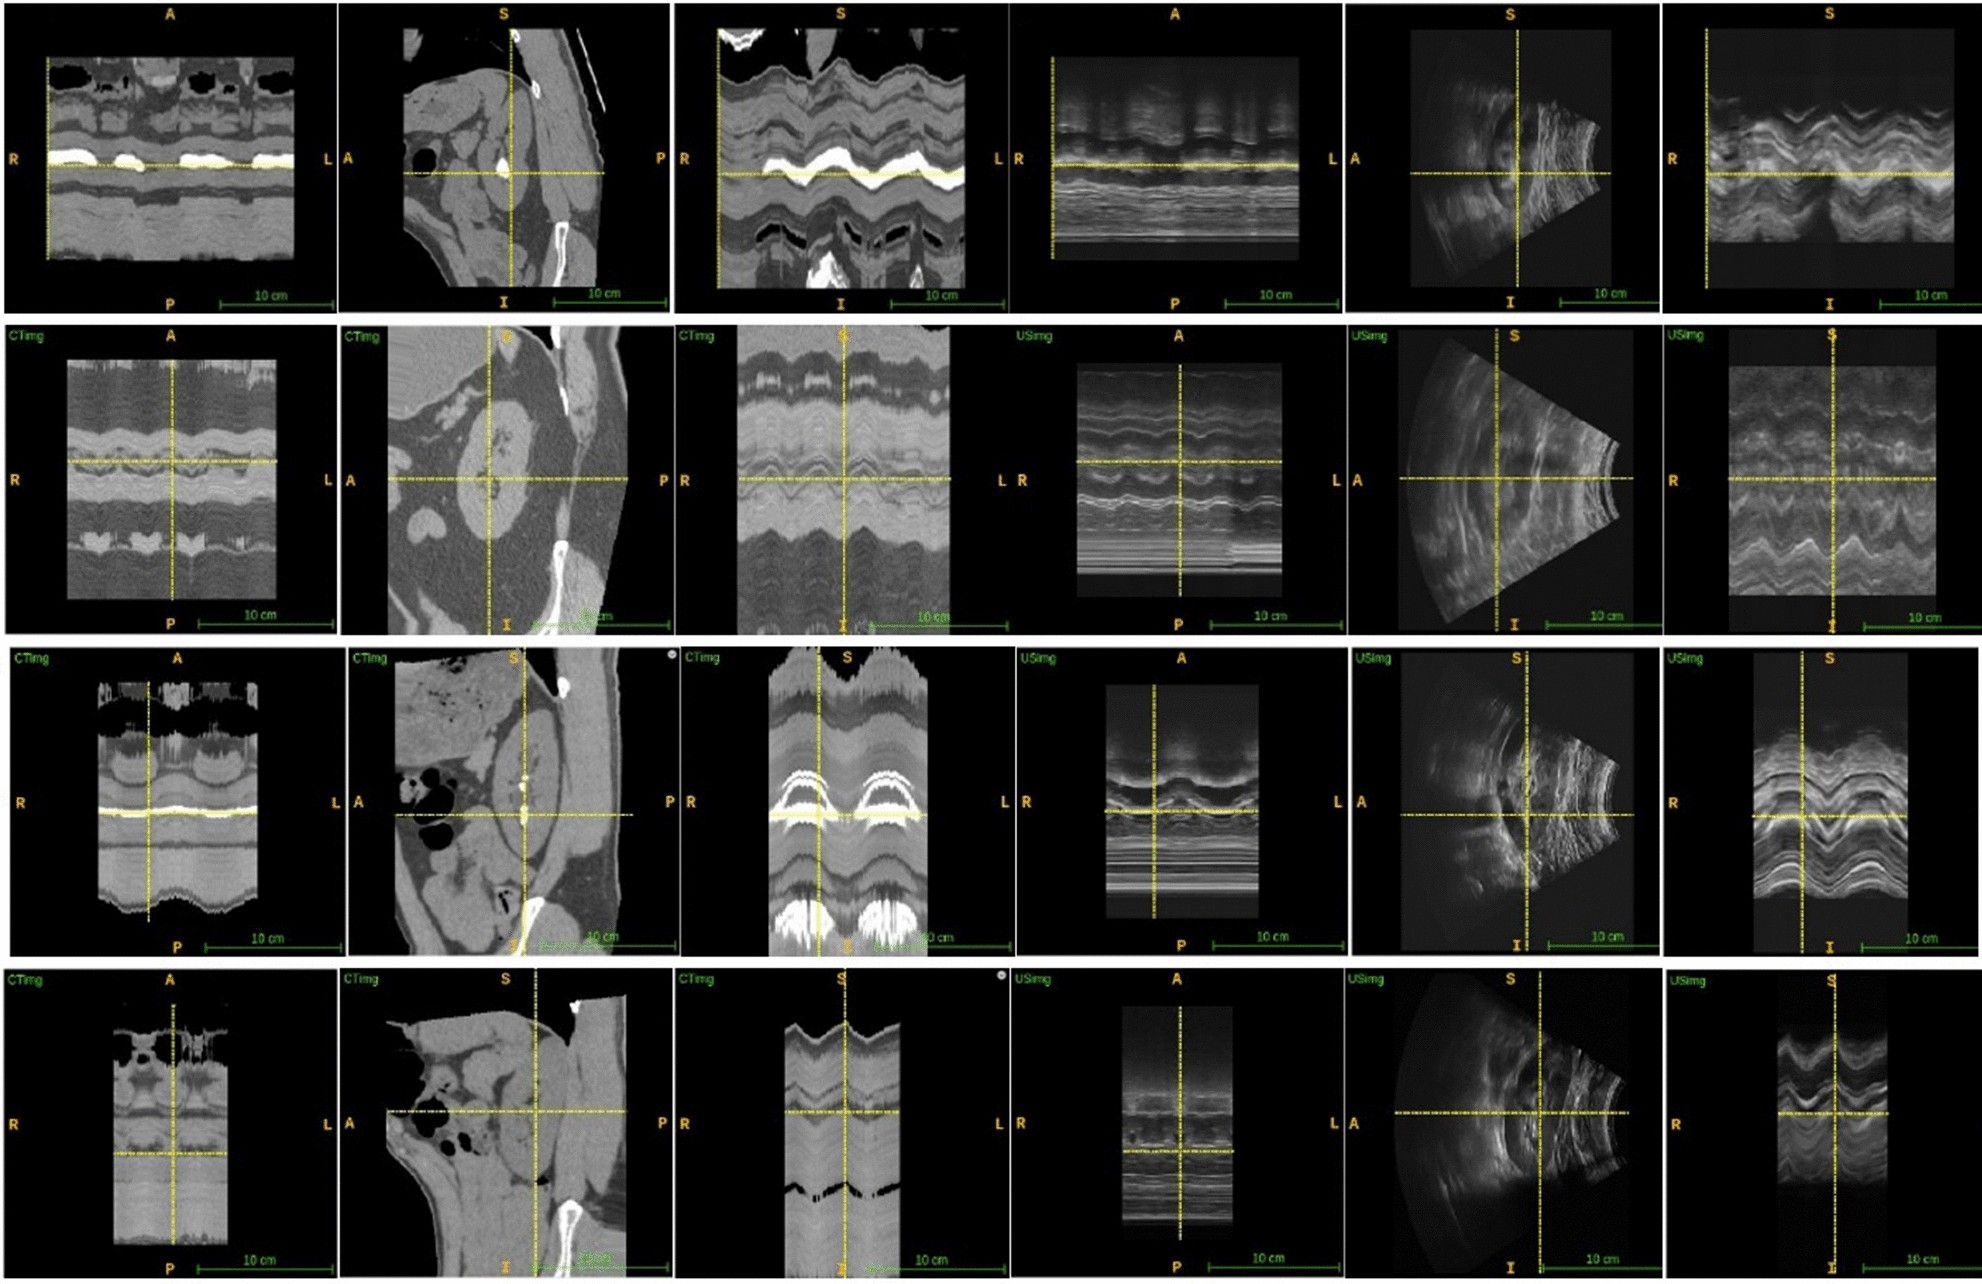

Figure 2

Example registration results, from left to right, the images are CT axial view, CT sagittal view, CT coronal view, U/S axial view, U/S sagittal view, U/S coronal view. Rows 1 and 3 visualized internal alignment of renal stone (crosshairs in the sagittal view). Rows 2 and 4 visualized slice alignment on inspiration and expiration (crosshairs in the coronal view).